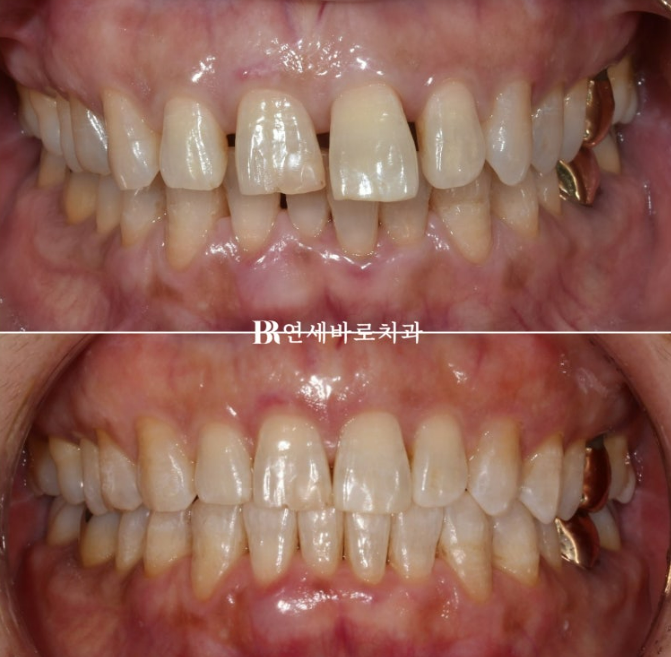

50대 치아벌어짐 6개월 간 치료 후 마무리 하였습니다.

인비절라인은 1차 치료가 끝난 후 디테일한 부분들을 수정하는 추가장치를 제작하는 경우가 많습니다.

이 분은 워낙에 장치를 잘 껴주시고 치아 이동도 원활한 편이라 추가장치 없이 마무리가 되었습니다.

23.01~23.07

점점 돌출이 되었던 앞니가 다시 뒤로 들어가면서 제자리를 찾았습니다.

50대 치아벌어짐 적절한 치료계획과 적당한 갯수의 올바른 어태치먼트의 배치

각 치아마다 다른 전략을 세워 치료를 하면 가장 빠르고 좋은 결과를 만듭니다.